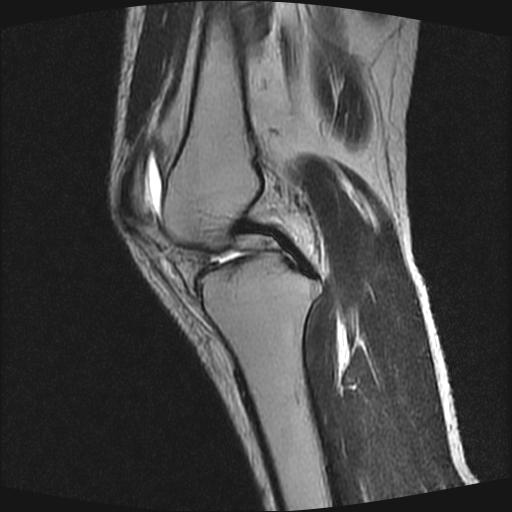

标题: MRI1265:男性40岁,右膝关节 [打印本页]

标题: MRI1265:男性40岁,右膝关节

40岁男性,右膝关节外伤,x光平片示,髁间隆突撕脱骨折。

1、前交叉韧带撕裂;

2、外侧半月板后角撕裂;

3、关节腔积液。

前交叉韧带撕裂,关节腔积液.

半月板1-2级损伤   前交叉韧带撕裂伤   关节腔少量积液  诸骨未见新鲜外伤性改变

髁间隆突撕脱骨折;内侧副韧带损伤。

内侧副韧带撕裂及关节腔积液是肯定的,但是前交叉撕裂确定吗?会不会有容积效应的因素,因为前一张前交叉显示清楚,连续性良好,且较光滑。请问楼主有关节镜支持吗?我们医院也经常有这样的患者,但苦于没有关节镜,而无法对照、证实(除非完全断裂),出现了不同的诊断结果只能毫无意义的争论。

1、前交叉韧、内侧副韧带撕裂;

3、关节腔积液。4、髁间脊撕脱骨折。

除了关节积液外并无韧带撕裂,acl胫侧附着点有2束,正常情况下脂肪信号。此病例应加做压脂像以便观察是否有骨损伤。